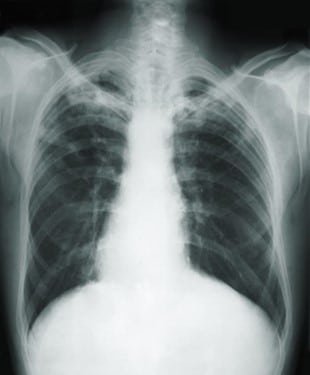

The posteroanterior (PA) chest x-ray, revealed pathologic changes in the lung field of a TB patient

TB blood tests are also called interferon-gamma release assays or IGRAs. Two TB blood tests are approved by the U.S. Food and Drug Administration. If the test results are positive, the patient has active or latent TB. If the test results are negative, the patient’s blood did not react to the test, and latent TB is unlikely.

These blood tests are safe during pregnancy. TB blood tests (IGRAs) are not affected by prior BCG vaccination and are not expected to give a false-positive result in individuals who have received BCG. TB blood tests are the preferred method of TB testing for people who have received the BCG vaccine.